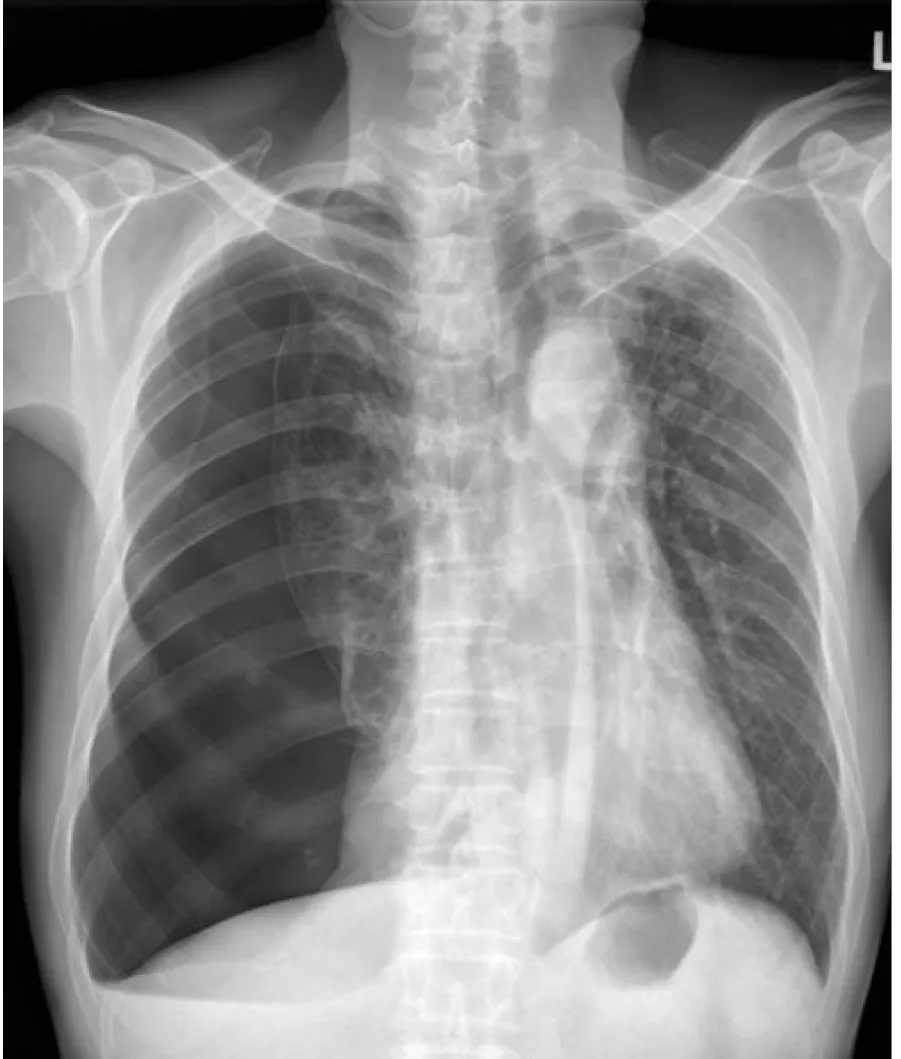

詳解

破題關鍵

這張胸部X光片最關鍵的發現是右側肺部明顯塌陷,並且可以看到清晰的臟層肋膜線(visceral pleural line),這明確指示了氣胸的存在。

選項拆解